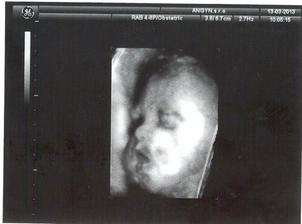

3.4.2013 - 31tt. návšteva poradne, USG, 1779 gramov, 3D úspešné, smiala sa a vyplazovala jazyk